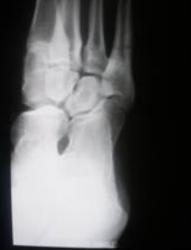

Протокол исследования. Левая стопа в пределах нормы. Справа определяется аномалия развития стопы в виде истинной четырехпалости (отсутствие 5 плюсневой кости и фаланг 5 пальца) – 1. Определяется гипоплазия фаланг пальцев, плюсневых костей и других костей стопы по сравнению с левой стороной. На рентгенограмме стопы, произведенной в косой проекции (2) чётко дифференцируются медиальная, промежуточная и латеральная клиновидные кости. Кубовидная и ладьевидная кости не дифференцируются. Определяется некоторая деформация и гипоплазия передних отделов таранной и пяточной костей. На боковой рентгенограмме стопы (3), произведенной в положении стоя (под нагрузкой) щель подтаранного сустава не дифференцируется, что свидетельствует о частичном синостозе между указанными костями. Головка таранной кости несколько укорочена, деформирована, уплощена с выраженным субхондральным склерозом. Она сочленяется с задней поверхностью медиальной, промежуточной и частично латеральной клиновидными костями

Заключение: Аномалия развития правой стопы в виде истинной четырехпалости, с отсутствием кубовидной и ладьевидной костей, частичным синостозом между пяточной и таранной костями. Гипоплазия костей правой стопы. Продольное плоскостопие второй ст.